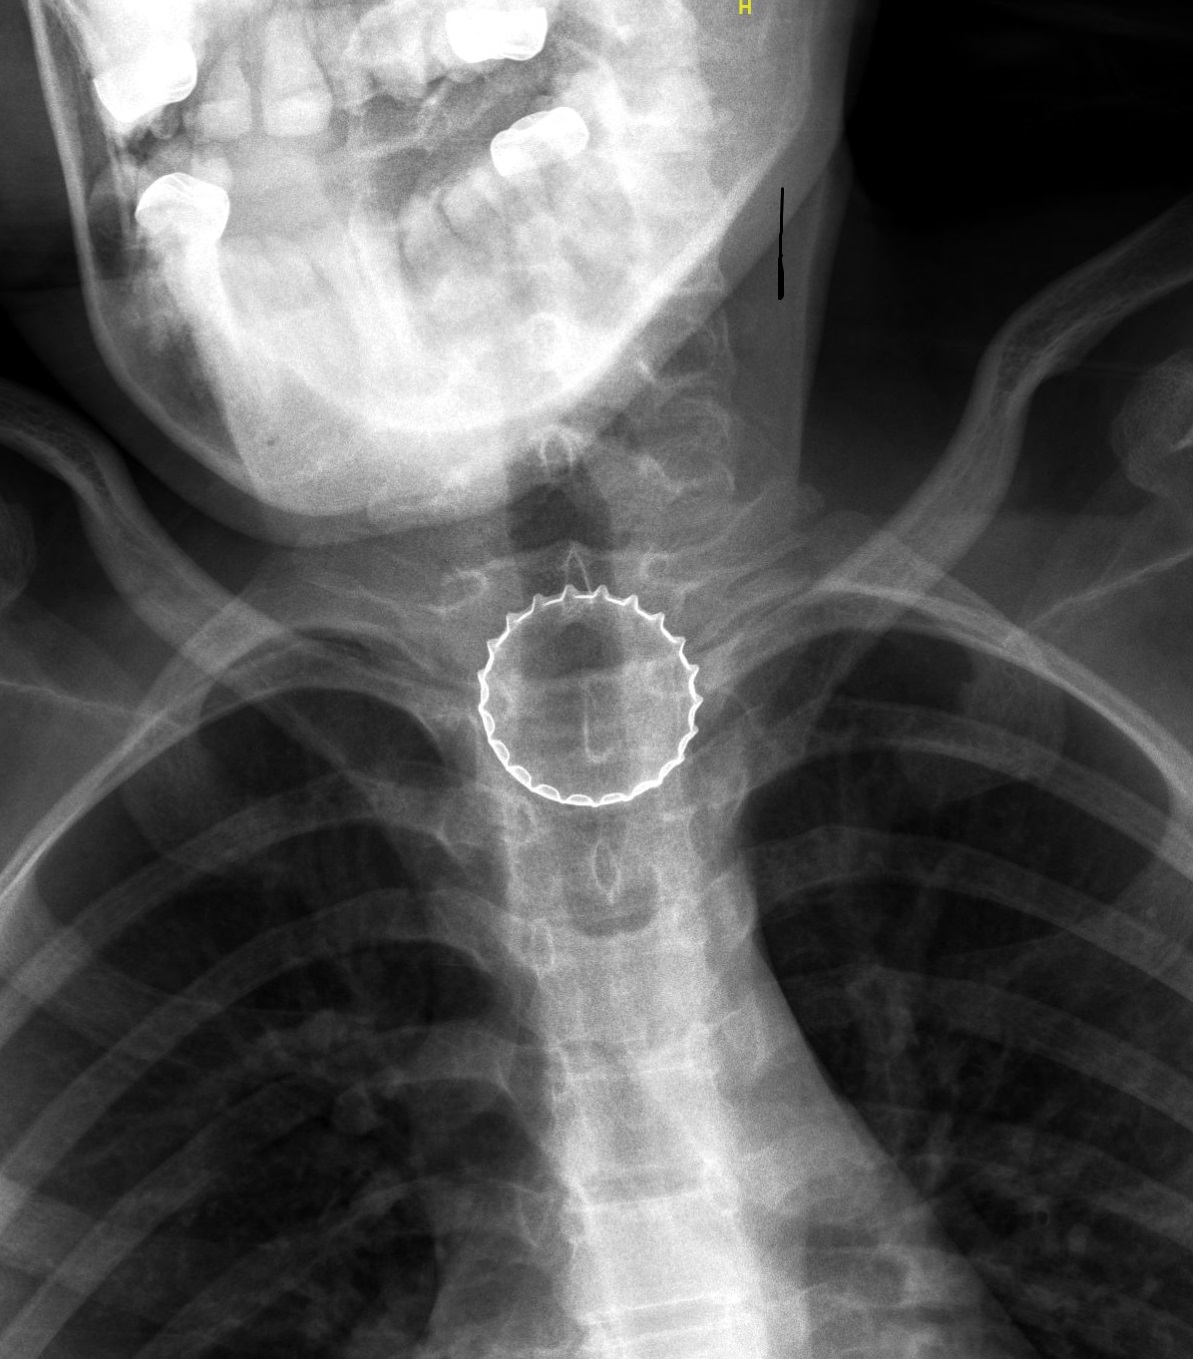

צילום רנטגן בו ניתן לראות את הפקק בוושט (צילום באדיבות המרכז הרפואי לגליל)

במיון ילדים עברה הנערה בירור מקיף ויסודי ע"י צוות בראשות ד"ר עלי ח'טיב, מומחה ברפואת ילדים, ובין השאר בוצע לה צילום רנטגן, בו התגלה גוף זר בוושט. הנערה הוכנסה לחדר ניתוח, שם – באמצעות ציוד אנדוסקופי ייעודי – הוצא מצינור הוושט פקק של בירה קורונה ע"י צוות ממחלקת אף אוזן גרון וניתוחי ראש-צוואר, בניהולו של ד"ר אייל סלע. הנערה אושפזה להשגחה למשך יממה ושוחררה במצב טוב.